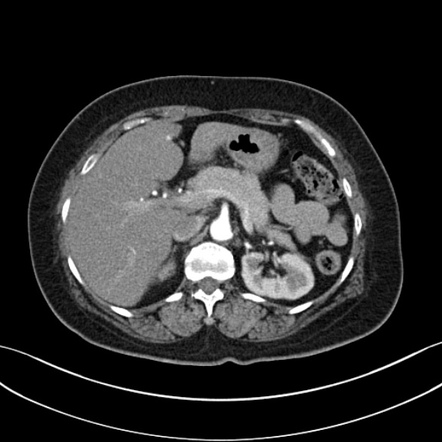

Three cases of pancreatitis are presented in which the diagnosis can be suggested by the appearance of a distinct radiolucent halo about the left kidney on the . Of edematous fluid into the anterior perirenal space may create a mass effect and a halo sign . Three cases of pancreatitis are presented in which the diagnosis can be suggested by the appearance of a distinct radiolucent halo about the left kidney on . Extension of edem atous fluid into the anterior perirenal space may create a mass effect and a halo sign with sparing of the perinephric fat 27. Bilateral renal halo sign in acute pancreatitis.

Extension of edem atous fluid into the anterior perirenal space may create a mass effect and a halo sign with sparing of the perinephric fat 27. Misuse presented with acute abdominal pain, vomiting, and a tense and tender abdomen. Of edematous fluid into the anterior perirenal space may create a mass effect and a halo sign . Bilateral renal halo sign in acute pancreatitis. Three cases of pancreatitis are presented in which the diagnosis can be suggested by the appearance of a distinct radiolucent halo about the left kidney on the . Three cases of pancreatitis are presented in which the diagnosis can be suggested by the appearance of a distinct radiolucent halo about the left kidney on . The clinical signs of acute pancreatitis are nonspecific,. This halo is produced by apparent enhancement of the perirenal fat by an adjacent retroperitoneal exudate in the left anterior pararenal space, .

This halo is produced by apparent enhancement of the perirenal fat by an adjacent retroperitoneal exudate in the left anterior pararenal space, . Misuse presented with acute abdominal pain, vomiting, and a tense and tender abdomen. Extension of edem atous fluid into the anterior perirenal space may create a mass effect and a halo sign with sparing of the perinephric fat 27. Of edematous fluid into the anterior perirenal space may create a mass effect and a halo sign . The clinical signs of acute pancreatitis are nonspecific,.